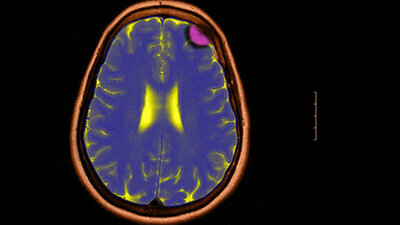

Computertomografie: Der Kopf des Patienten liegt im Aufnahmegerät, das spezielle Röntgenbilder vom Gehirn und möglichen Tumoren liefert.

Diagnose und Therapie: Der Hals-Nasen-Ohren-Arzt oder der Neurologe stellt den Tumor mit Hilfe von bildgebenden Verfahren wie Computertomografie und Magnetresonanztomografie (Kernspintomografie) fest. Ebenso kann zusätzlich eine Darstellung unter Einsatz eines Kontrastmittels (Angiografie) oder eine nuklearmedizinische Untersuchung (Positronen-Emissions-Tomografie, kurz PET) sinnvoll sein.

Diagnose und Therapie: Daignose und Therapie übernehmen meist Fachärzte für Hals-Nasen-Ohren-Heilkunde, oft im Team mit Spezialisten für Kopf- und Halschirurgie, sogenannten Otoneurochirurgen, und/oder Mund-Kiefer-Gesichtschirurgen. Aufschlussreich für die Diagnose sind neben den klinischen Befunden bildgebende Verfahren wie Magnetresonanztomografie, Computertomografie und Ultraschall sowie feingewebliche Untersuchungen im Labor, insbesondere nach Entfernung der Drüse. Danach wird die weitere Therapie festgelegt. Je nach Tumorart und Stadium kann zum Beispiel eine sich anschließende Strahlentherapie angezeigt sein (bei gutartigen Tumoren genügt im Allgemeinen deren Entfernung).

Diagnose und Therapie: Die Diagnose erfolgt mit bildgebenden Verfahren wie Magnetresonanztomografie oder Computertomografie.